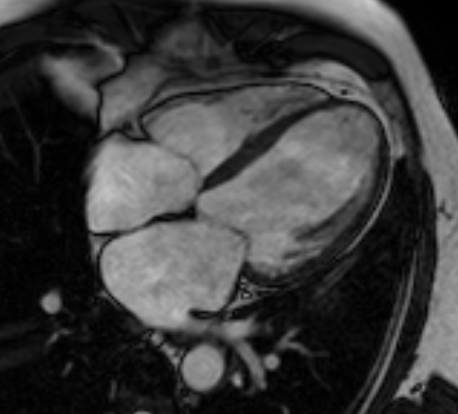

To start with, the Cardiac MRI images from multiple patients diagnosed with Pulmonary Hypertension were obtained.

If you’re new to this imaging technique, you’d be surprised how detailed the images obtained by it are!

Take a look below.

(If you’re curious about how MRI works, check out one of my previous articles on this topic.)

Next, the Cardiac MRI images were processed to identify and track the 3D motion of the ventricles of the heart using segmentation.